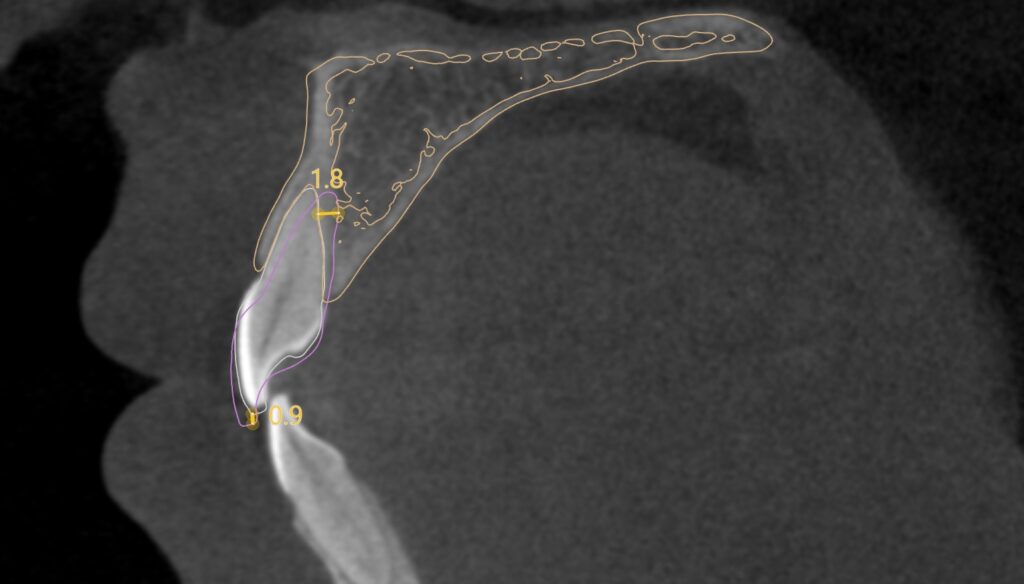

• CT segmentat și suprapus cu suprafețele dinților din scanare

• Raport rădăcini os